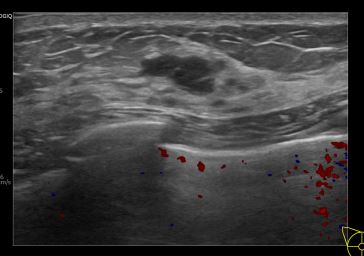

상기환자는 유방 추적 관찰 위해 내원하신 40대 후반 여성분으로 의심스러운 우측 혹 조직검사 시행해 유방암 진단되었습니다.